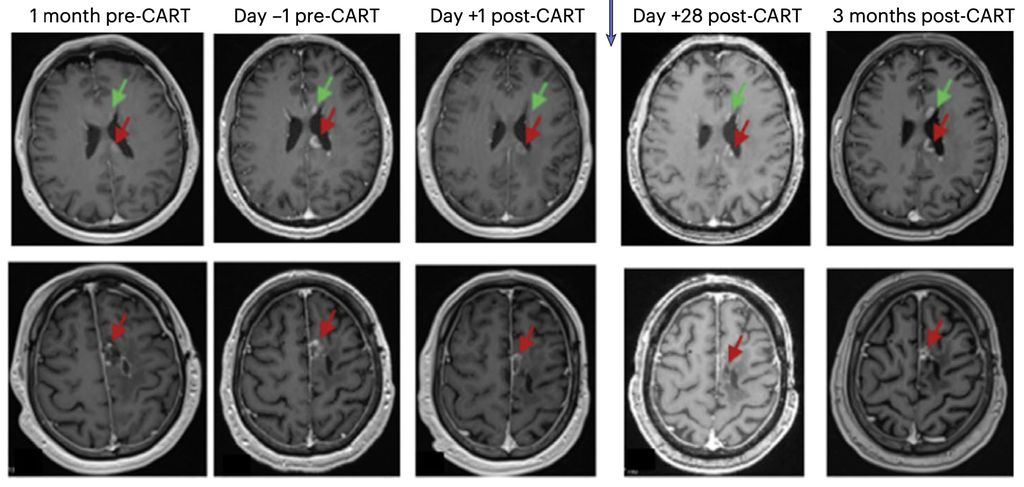

«Zu den Herausforderungen bei diesen Tumoren gehören die Heterogenität der exprimierten Tumorantigene und das immunsuppressive Tumormilieu», erklärte Prof. Dr. med. Denis Migliorini (Genf, Schweiz). Im vergangenen Jahr erregten verschiedene Publikationen zum Einsatz von CAR-T-Zellen beim Glioblastom grosse Aufmerksamkeit. Darunter war eine PhaseI-Studie zu intrathekal verabreichten CAR-T-Zellen, die sowohl gegen den epidermalen Wachstumsfaktor-Rezeptor (EGFR) als auch den Interleukin-13-Rezeptor-α2 (IL13Rα2) gerichtet sind (Abb.1).3

Abb. 1: Beispiel der MRT eines Patienten mit Glioblastom von einem Monat vor Verabreichung der CAR-T-EGFR-IL13Rα2-Zellen (Dosis-Level 2) bis zu drei Monaten nach der Verabreichung der CAR-T-Zellen. Axiale Gadolinium-verstärkte T1-gewichtete Bilder zeigten am Tag –1 vermehrt verstärkte Krankheitsherde, auch im Corpus callosum (oberes Feld, roter Pfeil), entlang der ependymalen Oberfläche des linken Seitenventrikels (oberes Feld, grüner Pfeil) und um die der linken frontalen Resektionshöhle (unteres Feld, roter Pfeil). Am Tag +1 aufgenommene Bilder, die vor der Verabreichung von Steroiden aufgenommen wurden, zeigen einen Rückgang an allen Stellen. Die Läsionen waren am Tag +28 stabil und blieben zum 3-Monats-MRT-Zeitpunkt unverändert (Quelle: Bagley SJ et al. 2024)3

«Wie wir anhand der Daten der ersten sechs Teilnehmenden dieser Studie gesehen haben, zeigte die Behandlung eine unmittelbare, potente Antitumoraktivität», so der Redner. Allerdings war die Ansprechdauer kurz und es wurde eine signifikante, wenn auch in allen Fällen reversible Neurotoxizität beobachtet. Prof. Migliorini und sein Team suchten gezielt nach weiteren Antigenen, die als Zielstrukturen für eine CAR-T-Zell-Therapie infrage kommen. Ihre Wahl fiel auf PTPRZ1 («protein tyrosine phosphatase receptor type Z1»).4 Zudem entschieden sie sich für eine mRNA-basierte Herstellung der CAR-T-Zellen, im Gegensatz zum üblichen Vorgehen der viralen Transduktion.